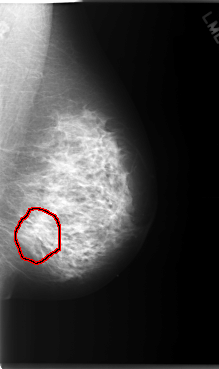

LEFT_MLO LINES 5904 PIXELS_PER_LINE 3504 BITS_PER_PIXEL 12 RESOLUTION 50 OVERLAY

FILE: C_0070_1.LEFT_MLO.OVERLAY

TOTAL_ABNORMALITIES 1

ABNORMALITY 1

LESION_TYPE MASS SHAPE ARCHITECTURAL_DISTORTION MARGINS N/A

ASSESSMENT 4

SUBTLETY 1

PATHOLOGY MALIGNANT

TOTAL_OUTLINES 1

BOUNDARY

FILE: C_0070_1.LEFT_CC.OVERLAY

LESION_TYPE MASS SHAPE IRREGULAR MARGINS ILL_DEFINED

SUBTLETY 3